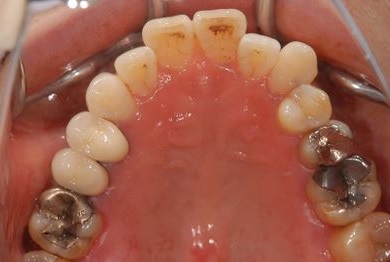

インプラント治療+セラミック治療

| カテゴリー | 【インプラント治療】【セラミック治療】 | ||||||||||||||||||||||||||||||||

| 性別/年齢 | 女性 / 61歳 | ||||||||||||||||||||||||||||||||

| 主訴 | 奥歯がぐらつく。 | ||||||||||||||||||||||||||||||||

| 治療方針 | インプラント治療にて機能的・審美的回復を行う。 | ||||||||||||||||||||||||||||||||

| 治療内容 | インプラント1本、メタルボンドセラミッククラウン3本(メタルボンドセラミック用土台2本) | ||||||||||||||||||||||||||||||||

| 総治療費 | 625,538円 | ||||||||||||||||||||||||||||||||

| 治療期間 | 1年0ヶ月 |